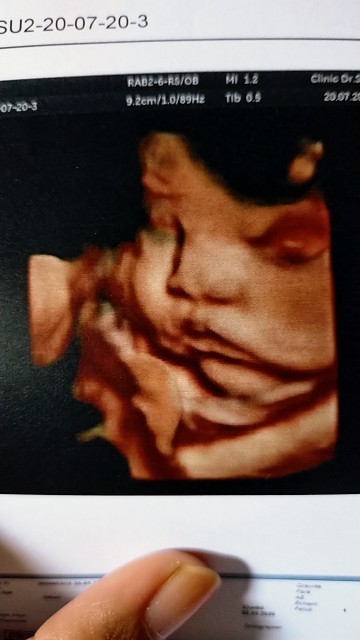

มาอวดภาพอัลตร้าซาวด์กันหน่อยแม่จ๋า 🤰🏻👼🏻 ชาย หรือ หญิง กันนะ?

ชายคับ

ชายค่ะ

ผู้ชาย